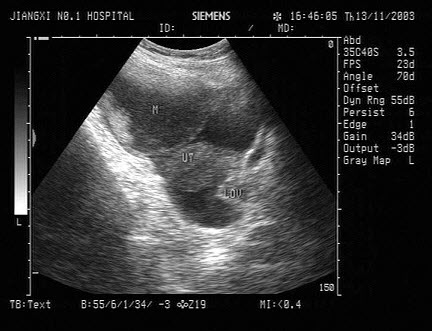

B.膀胱内血块

女性,25岁,停经47天,阴道不规则出血1周。尿妊娠试验阳性。结合超声图像,最可能的诊断为()

A.附件炎性包块

B.宫外孕

C.卵巢癌

D.子宫肌瘤

E.畸胎瘤